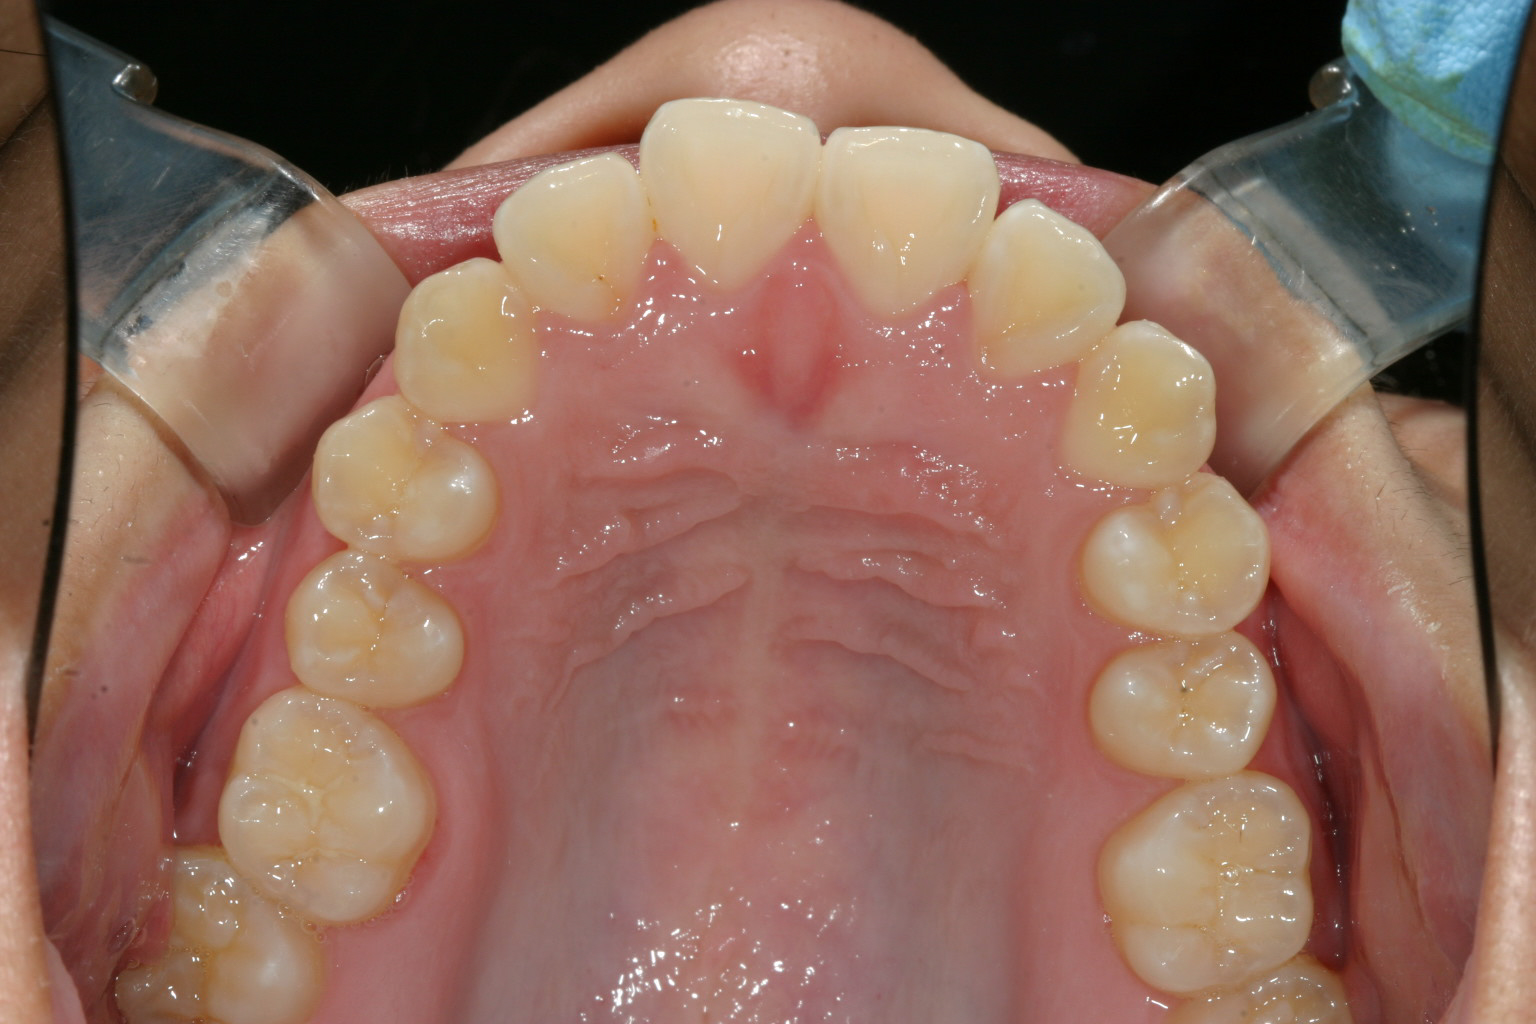

咬合面観はさほど悪く無いように見えます。